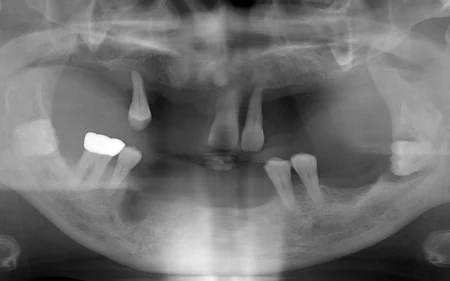

拝見したところ、歯を支える顎の骨が溶ける重度の「歯周病」が原因で、残っているすべての歯がグラグラと揺れており、保存が難しい状態でした。

しっかり噛めるようにするためには、人工の歯根を顎の骨に埋め込む「インプラント」を用いた治療法が適していると判断しました。

重度の歯周病が進行していて、どの歯もグラグラ揺れていました。 すべての歯を抜く必要がありました。